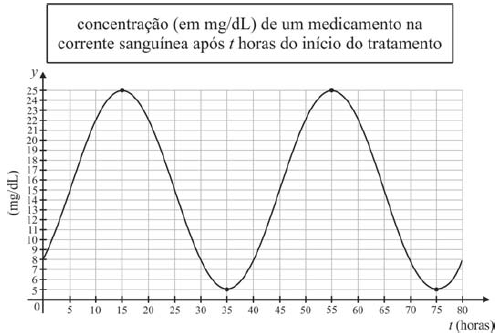

O gráfico da função y = C(t) acima apresentado descreve o nível de concentração, em mg/dL, de determinado medicamento na corrente sanguínea de um paciente, em função do tempo t em horas, durante o período de 80 horas. O instante t = 0 corresponde ao momento do início do tratamento, quando o medicamento foi injetado no paciente pela primeira vez e C(0) = C(80) = 8 mg/dL. Considere essas informações e, ainda, que t = 0 corresponde às 10 h da segunda-feira, t = 1 às 11 h do mesmo dia, e assim sucessivamente, e que o medicamento seja injetado toda vez que sua concentração na corrente sanguínea atingir 5 mg/dL. Com relação a essa situação, assinale a opção correta.